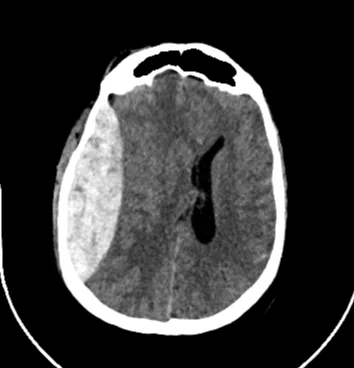

Διάγνωση με CT — τι κοιτάμε στην απεικόνιση;

Η CT εγκεφάλου είναι η εξέταση “κλειδί”. Το μέγεθος και τα χαρακτηριστικά (όγκος/πάχος/μετατόπιση) του αιματώματος έχουν πρακτική σημασία στην λήψη των κλινικών αποφάσεων.

Η CT εγκεφάλου αποτελεί την εξέταση εκλογής. Το επισκληρίδιο αιμάτωμα απεικονίζεται τυπικά ως αμφίκυρτη (φακοειδής) υπέρπυκνη συλλογή η οποία δεν διασχίζει τις κρανιακές ραφές, μιας και η σκληρά μήνιγγα προσφύεται στενά στο οστό.

Στη Neuroknife δίνουμε ιδιαίτερη σημασία σε 3 απεικονιστικές μετρήσεις που επηρεάζουν άμεσα τις θεραπευτικές αποφάσεις:

• Όγκος αιματώματος (σε mL),

• Πάχος θρόμβου (σε mm),

• Μετατόπιση δομών μέσης γραμμής (MLS) (σε mm) και απεικόνιση των βασικών δεξαμενών του εγκεφάλου.

Επίσης αξιολογούμε συστηματικά: πιθανές συνυπάρχουσες κακώσεις (θλάσεις, υπαραχνοειδή αιμορραγία, υποσκληρίδιο αιμάτωμα), καθώς και την παρουσία/πορεία συνοδού κατάγματος, ιδίως όταν αυτό διέρχεται μέσω αγγειακών δομών.